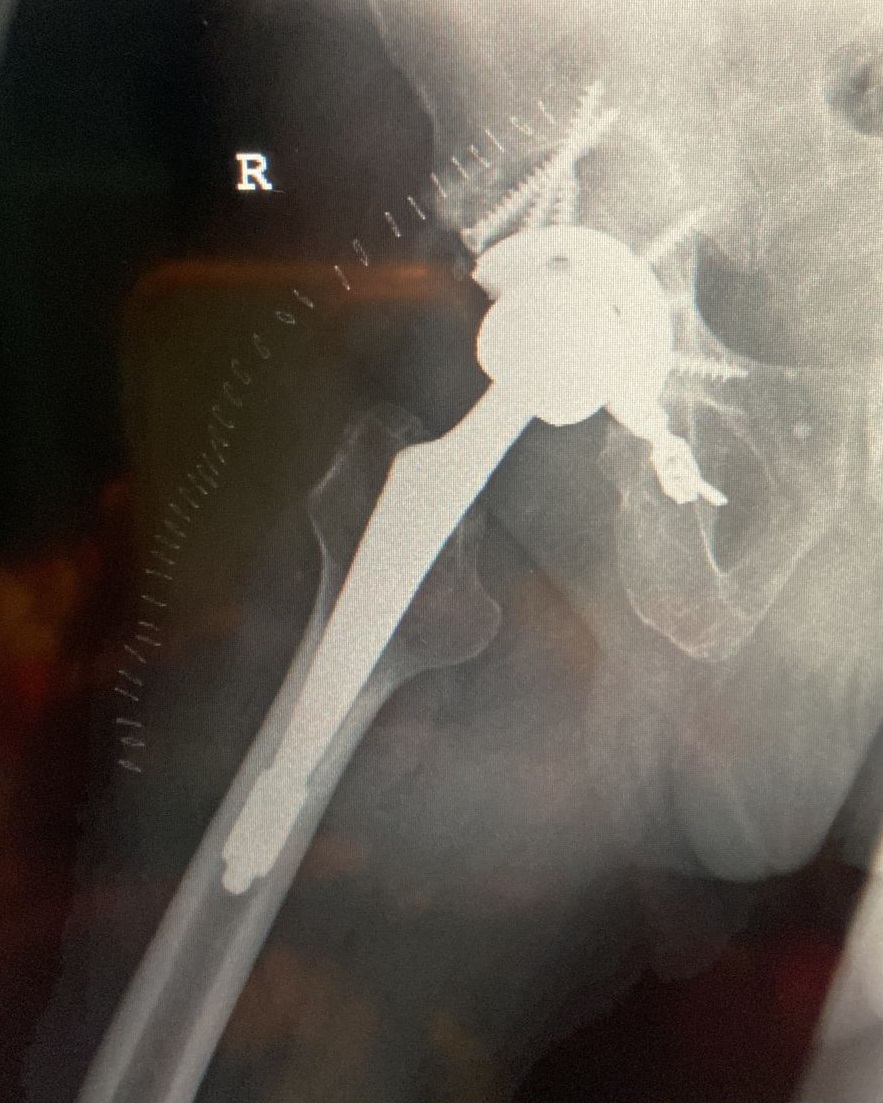

71-year old male with a right total hip following fracture dislocation 21 years ago presents with a 6 month history of increasing pain and shortening of the right lower limb. Recommended for acetabulum revision. Performed with graft multi hole revision cup and change of femoral head to 36 mm